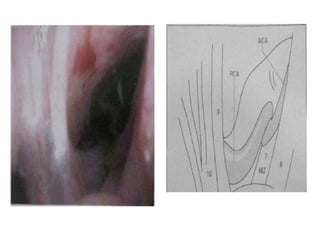

Right sided anterior petrosectomy on a cadaver dissection: intradural exposure

and operative field. PCA Petrous carotid artery; DPA drilled petrous apex; IPS

inferior petrosal sinus; BA basilar artery; VI 6th cranial nerve; AICA anterior inferior

cerebellar artery; P pons; V 5th cranial nerve